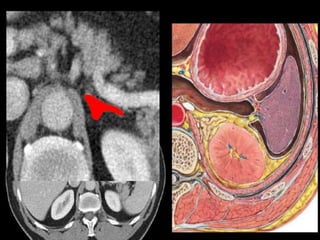

CT – computed tomography.

•Cross-sectional modality

with capabilities for

multiplanar reconstruction

and dynamic imaging to

assess vascularity

•Tube rotates around the

body and a circle of

stationary detectors detects

the penetrating x-rays

forming an image.

CT – computedtomography. •Cross-sectional modality with capabilities for multiplanar reconstruction and dynamic imaging to assess vascularity •Tube rotates around the body and a circle of stationary detectors detects the penetrating x-rays forming an image.